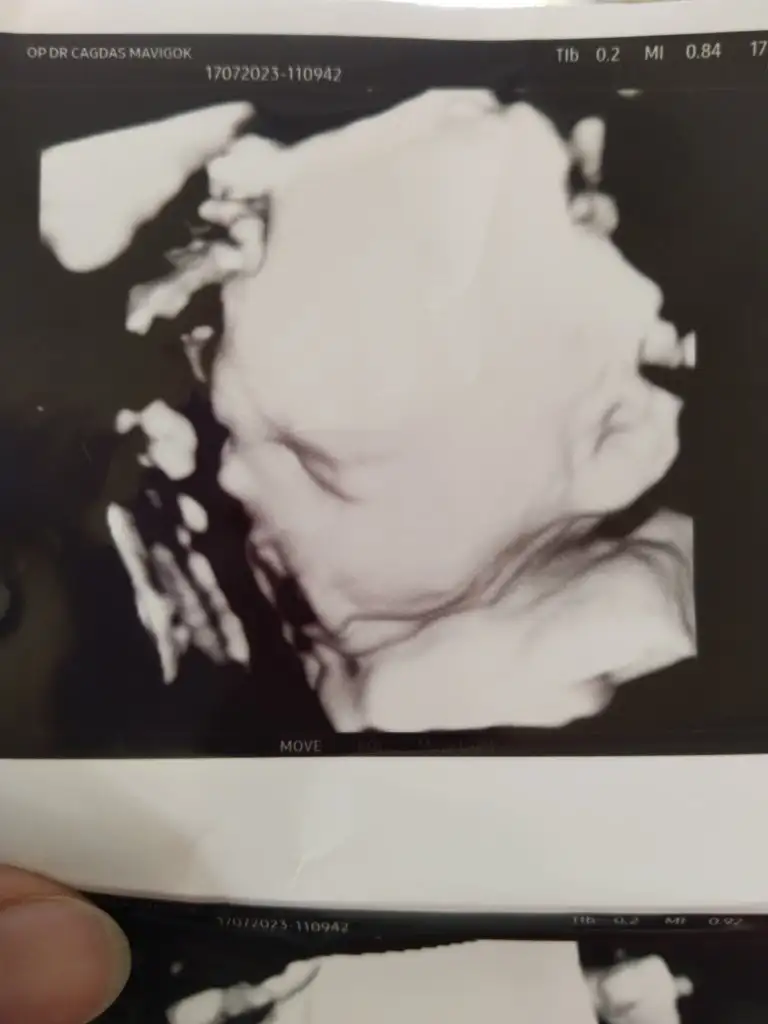

Bende bugün doktora gittim kızlar ogluşum yüzünü yan profilden gösterdi biraz 😅 Kimseye benzetemedik 🥹 bakalım ne çıkacak 🤣 1350 gram dedi 28+4 için iyidir umarım. Enfeksyon vs geçmiş çok şükür 🙏, herşey yolunda gidiyor. Doktora soramadım unutmusum. Bu haftalar araba ile uzun seyahatler için uygun mu acaba 🙄 birşey olur mu ?

Oy maşallah 🧿☺️ nasıl yaslamış yüzünü benimkide eliyle kapatıyordu 😅😅